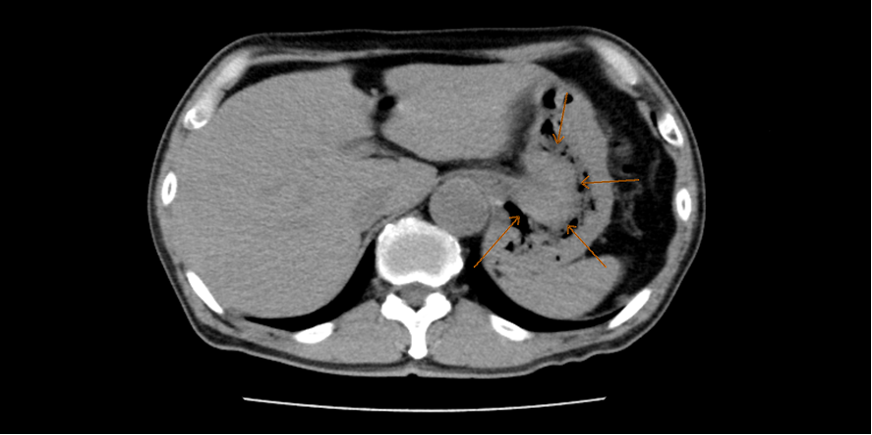

膵臓がんは特徴的な症状がなく、早期発見が難しいがんの一つです。早期には自覚症状がほとんどなく、病気が進むと、胃部不快感、腹痛、腰背部痛、黄疸、腹部違和感や食欲不振、体重減少、糖尿病の悪化などがみられます。現在、膵臓がんの原因ははっきりしていませんが、喫煙・膵嚢胞・糖尿病・慢性膵炎・膵臓がんの家族歴などが危険因子とされています。このような因子を持っている方は早期発見のため、積極的に血液検査やCT検査、MRI検査などを受けられることをお勧めします。